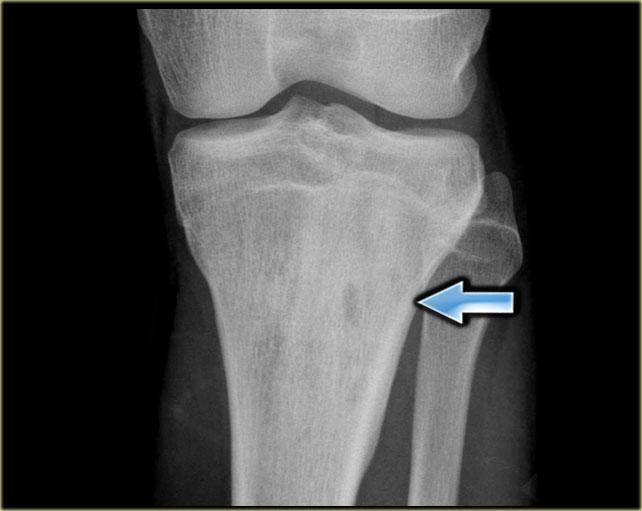

Đây là tổn thương ở vùng đầu xương, là hậu quả của hoại tử xương sau chấn thương.

Ở vùng đầu xương, chúng ta sử dụng thuật ngữ hoại tử vô mạch chứ không phải nhồi máu xương.